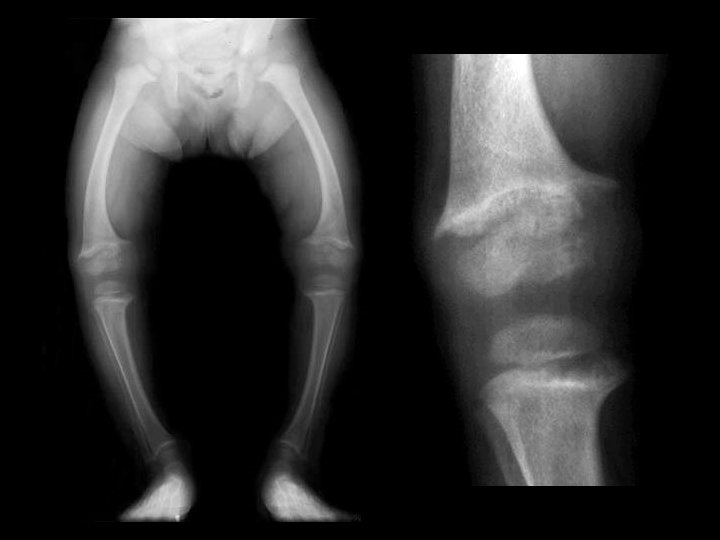

Rickets • Findings: – Cupped and frayed metaphyses – Wide physes (increased osteoid) – Long bone bowing – Decreased bone density • ddx: – NONE! – This is an Aunt Minnie!